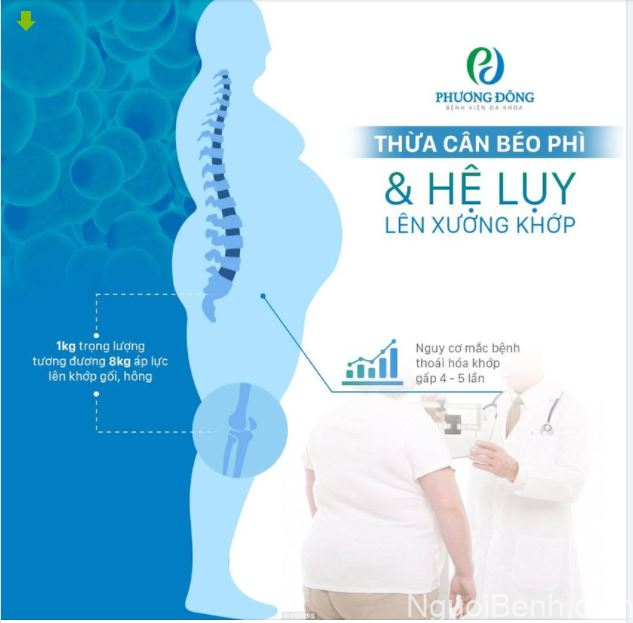

1.4. Thừa cân và ít vận động cũng gây ra tình trạng đau nhức xương khớp

Các nghiên cứu trên đã chỉ ra mối tương quan mật thiết giữa cân nặng và bệnh xương khớp. Việc thừa cân sẽ gây ra áp lực cho các khớp, nhất là vùng khớp gối, khớp háng và cột sống, khiến cơ thể thường xuyên đau nhức, khó khăn khi di chuyển. Về lâu dài, cơn đau có thể chuyển thành đau nhức mạn tính. [8]

Hệ lụy của việc thừa cân đối với cơ xương khớp